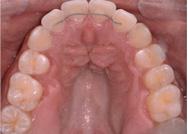

Se presenta un paciente de 19 años 10 meses diagnosticado con clase III esquelética hiperdivergente con desviación mandibular, colapso maxilar y mandibular severo, mordida cruzada posterior bilateral, clase III molar derecha e izquierda y clase III canina bilateral. Con los órganos dentarios OD 12, 15, 22 y 25 palatinizados, 35 y 45 lingualizados, apiñamiento superior e inferior, línea media inferior desviada 2 mm a la derecha respecto a la línea media facial. Tratamiento: expansión dentoalveolar, extracciones del premolar 15, alineación, nivelación, distalización, Stripping, detallado y retención. Aparatología utilizada: expansor en abanico, brackets prescripción Roth 0.022 × 0.028", bandas, tubos en primeros y segundos molares superiores, tubos bondeables en molares inferiores, botones linguales en 16,

14, 24, 33, 44, 46, microtornillo en Shelf mandibular 2 × 12 mm de acero Bioray. Objetivos: mejorar perfil labial, desarrollo transversal del maxilar y mandíbula, corrección de apiñamiento maxilar y mandibular, incorporar los órganos dentarios OD 12 y 22 al arco, obtener clase I molar derecha, mantener clase III molar izquierda, obtener clase I canina bilateral, corrección del overjet y overbite y de las líneas medias dentales, mantener relaciones esqueléticas, mejorar estado periodontal, lograr correcta intercuspidación, guía de desoclusión canina y guía incisiva, gingivoplastia generalizada, exodoncias OD 15, 35 Y 45. Tiempo de tratamiento: 3 años y 10 meses.

En los cortes tomográficos en la Figura 6 se muestra el colapso maxilar severo en la Figura 7 y mandibular severo con el tratamiento de conducto en el OD 36.

desviada 2 milimetros a la derecha, OD 12 y 22 palatinizados, en la Figura 9 vemos la clase III molar izquierda y derecha y la clase III canina bilateral, en la Figura 10 apreciamos las arcadas de forma triangular.

Resultados

Se lograron los objetivos planteados, durante el tiempo de tratamiento de 3 años y 10 meses, en la Figura 11 se puede observar que del lado derecho se obtuvo la clase I molar y se mantuvo la clase III molar izquierda, clase I canina bilateral, la línea media superior coincidente e inferior desviada 0.5 milímetros a la derecha al final del tratamiento, adecuada intercuspidación, en la Figura 12 la forma oval de la arcada superior e inferior.

Figura 10. Vista oclusal superior e inferior. Figura 11. Intraorales finales. Figura 12. Oclusales superior e inferior.